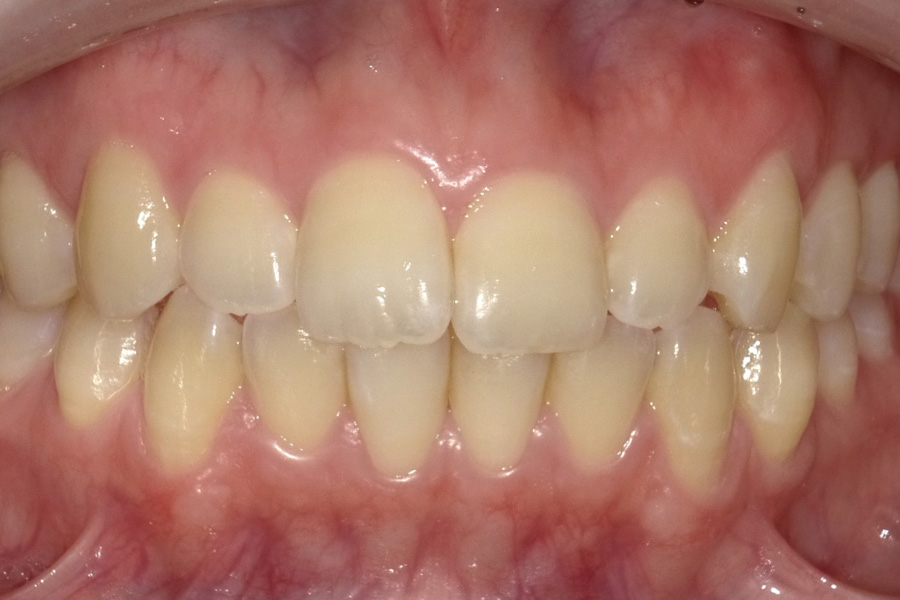

虫歯があるから削ったり悪くなったから抜くのではなく、まずは虫歯と歯周病が起きないようにより良い環境づくりをすること、そうすることによって歯を長く維持することが可能となります。

そのためには、健康状態に関する情報と生活習慣などの状況を把握したうえで、お口の中のリスク評価をおこないます。

その結果をもとに、お一人お一人にあった治療計画をご提案させていただきます。

ご自分の歯で食べ、話し、笑える幸せを生涯にわたり維持するためのお手伝いを全力でさせていただきます。